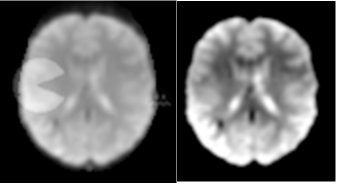

For a single example scan, Figure 5 shows the leverage and robust distance functions, along with 6 motion parameters (roll, pitch, yaw, and translation in each direction) and their derivatives, which are commonly used for artifact detection. Below the plot, the volumes corresponding to the spikes at time points 60, 90, 134 and 150 are shown. Three of the spikes are leverage and distance outliers using any of the thresholds considered ( for leverage; for robust distance), while the spike at time point 90 is only a leverage outlier at . Obvious banding artifacts are seen at time points 60 and 150, a moderate banding artifact is seen at time point 134, and no visible artifact is apparent at time point 90. While the artifact at time point 150 would be detected using motion measures, the other spikes would likely go undetected.